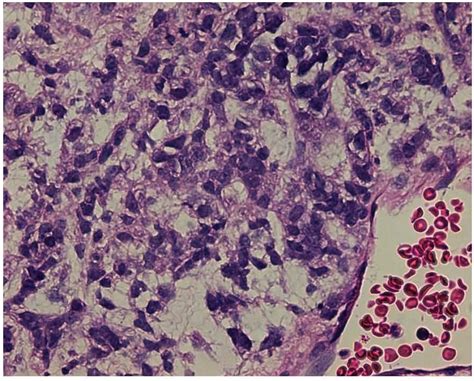

Because these tumors lack the differentiated features of normal tissue, pathologists often struggle to identify them using standard staining techniques. Diagnosis requires advanced molecular testing, specifically Fluorescence In Situ Hybridization (FISH) or immunohistochemistry for the NUT protein. Without these specific tests, a case of NMC might be incorrectly labeled as poorly differentiated squamous cell carcinoma, leading to inappropriate treatment protocols.